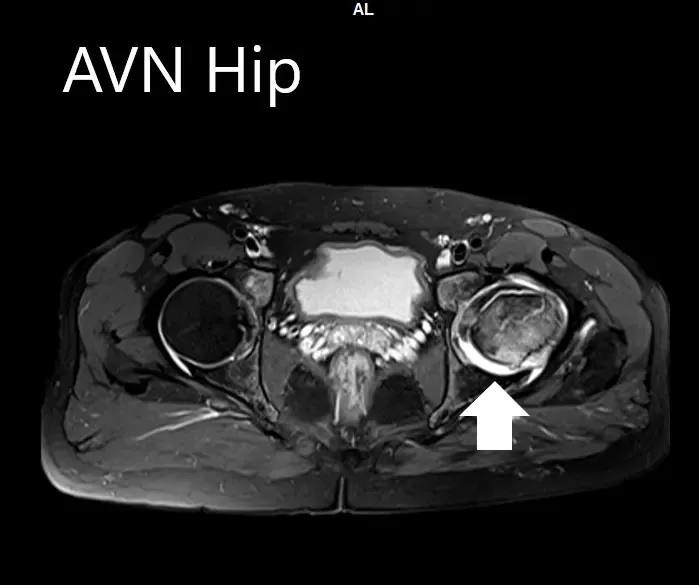

An MRI was obtained for diagnostic confirmation and staging of the disease. The left femoral head was collapsed with irregular contour and showed areas of altered signal intensity with a line of demarcation. Hypointense areas both on T1WI & T2WI seen in head suggestive of sclerosis. Surrounding marrow edema was seen

The left hip had advanced avascular necrosis with a collapse. The right hip was uninvolved presently. He was educated about the worsening collapse of the hip joint leading to his symptoms. Although the patient was young, he was advised a total hip replacement surgery in view of the collapse of the head of the femur with arthritis.